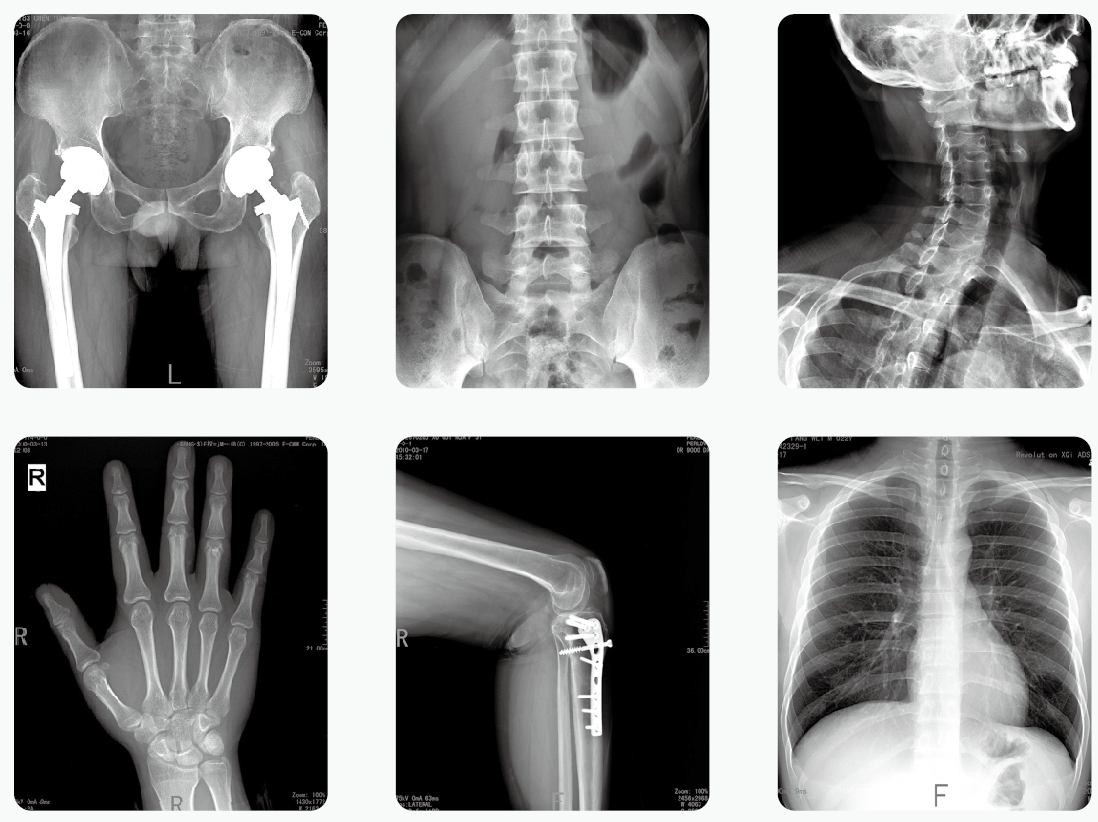

【产品临床图片】

移动式DR为移动式X射线摄影医疗诊断设备,可用于放射科摄影、影像科摄影、儿科摄影、体检摄影、手术室及重症监护室摄影,满足对人体关节、骨骼、胸部、泌尿、妇科和特殊部位的X射线摄影要求。

PLX5200移动式dr是一款高频组合式数字化X射线摄影医疗诊断设备,适用于放射科、骨科、病房、急诊室、手术室 、ICU等处,满足人体的头部、四肢、胸腔、脊柱、腰椎、腹部等全身各部位的数字化摄影的工作需求。